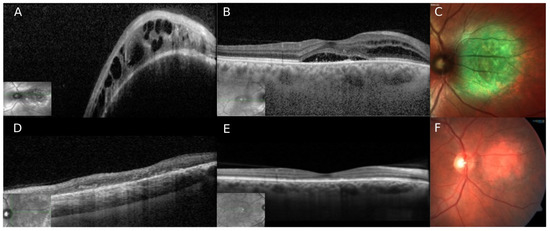

2. Case Number 1

3. Case Number 2

4. Case Number 3

5. Case Number 4